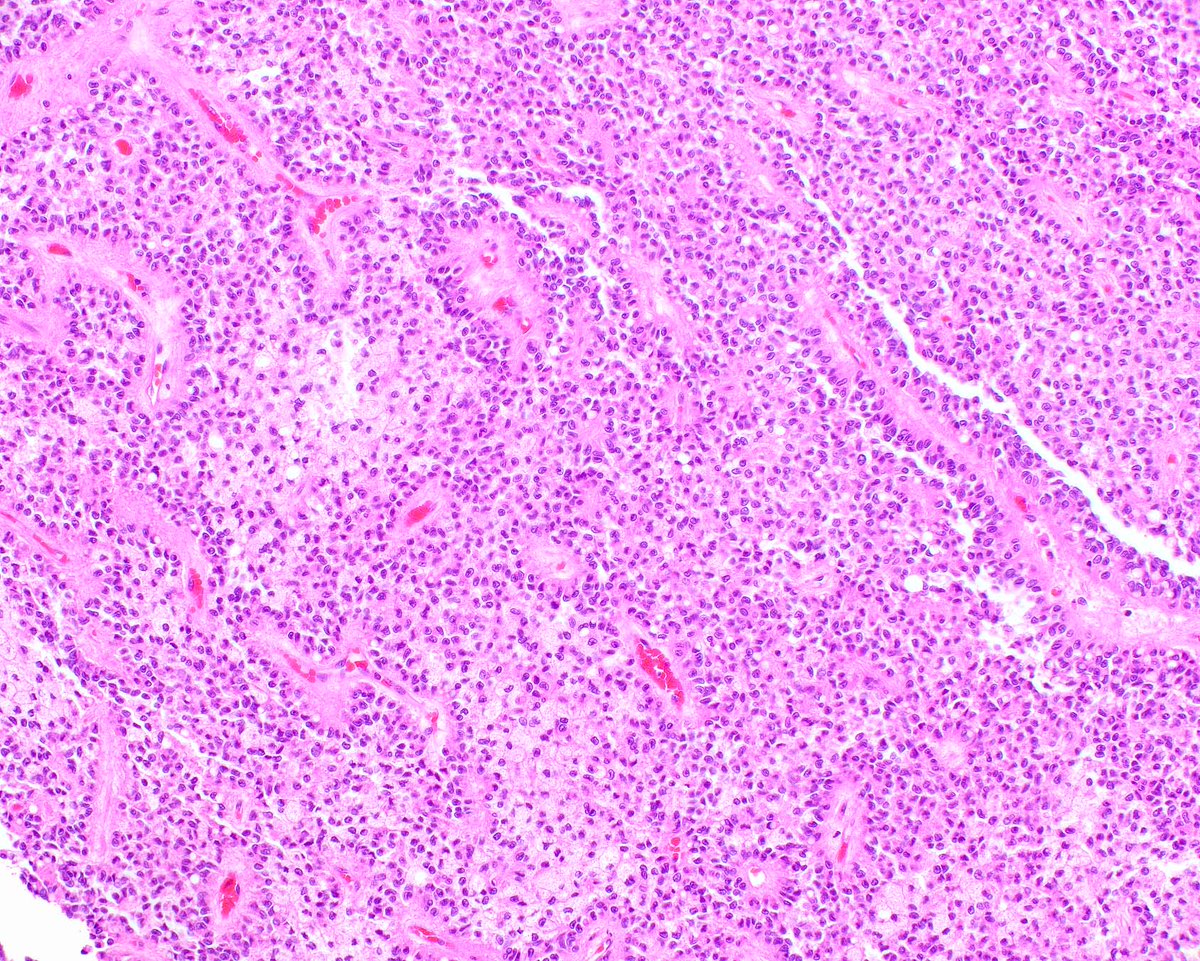

This is an ordinary mantle cell lymphoma of the colon - presenting as multiple nodular areas. However, more aggressive subtypes are in a spectrum with large B cell lymphomas.

Li S, Tang G, Jain P, Lin P, Xu J, Miranda RN, Cheng J, Yin CC, You MJ, Wang ML, Medeiros LJ. SOX11+ Large B-Cell Neoplasms: Cyclin D1-Negative Blastoid/Pleomorphic Mantle Cell Lymphoma or Large B-Cell Lymphoma? Mod Pathol. 2024 Feb;37(2):100405.PMID: 38104893.